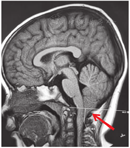

病例1,女,2岁7个月,因"长出气2周"于2021年3月11日就诊于呼吸科。患儿表现为白天运动后长出气,夜间刚入睡及晨起时叹气样呼吸,熟睡后呼吸规律,但有时出气粗,不打鼾,时轻时重。查体未见明显异常。心脏彩超、脑血管超声、肺CT、头颅CT均未见异常。PSG相关数据(图2、图3):(1)睡眠结构:总睡眠时间446 min,N1期睡眠37%,N2期睡眠28.8%,N3期睡眠13.8%,R期睡眠20.4%,睡眠潜伏期8 min,R睡眠潜伏期98.5 min,睡眠效率75.9%,入睡后清醒时间134 min。入睡后无鼾声,无张口呼吸,提示睡眠结构紊乱;(2)呼吸事件:OAHI 0次/h,CAI 111次/h,CA最长时间15 s,平均时间10 s,符合CSA;(3)血氧情况:≥3%氧减指数106.5次/h,平均血氧97%,最低血氧84%,<90%血氧时间占睡眠时间百分比0.2%;(4)觉醒指数:呼吸事件相关6.1次/h,肢体运动相关0次/h,自发觉醒3.6次/h;儿童OSA疾病特异性生活质量问卷(OSA-18):55分,轻度。实验室检查:血气分析(静脉血)pH 7.35,二氧化碳(carbon dioxide,CO2)分压39 mmHg(1 mmHg=0.133 kPa),氧分压40 mmHg,实际碳酸氢盐21.5 mmol/L,标准碳酸氢盐21.3 mmol/L,剩余碱-3.8 mmol/L,血氧饱和度72%。颅脑磁共振成像(magnetic resonance imaging,MRI)(图4):小脑扁桃体超过枕骨大孔水平约1.6 cm,延髓及上段颈髓略受压,脑实质内未见异常信号。诊断为Chiari畸形Ⅰ型,患儿采取保守治疗,定期复查,随访。

本研究结果发现,56例CSA儿童中,52例(92.9%)CAI在20次/h以下,与气道阻塞存在重叠的病理生理机制。CAI>20次/h有4例,均是出现了中枢神经系统病变,包括Chiari畸形1例,脑干肿瘤2例及遗传代谢病疾病1例。本研究报道的2例病例,均是在完善睡眠监测时,发现呼吸节律异常、间歇低氧、CO2潴留等表现,建议临床完善中枢神经系统查体及影像检查,查找引起CA的原因,最终明确诊断。